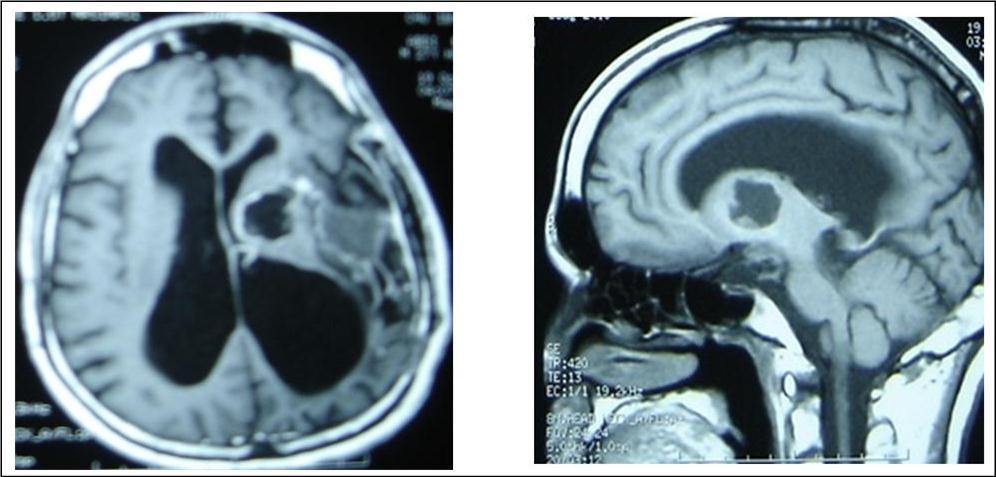

A 27 years-old male patient was admitted with 1 month history of headache, fever, short term memory lack, aphasia, right hemiparesis and seizures. He had liver hydatid cysts excised 8 years before and was treated with adjuvant medication (albendazole). The neurological examination revealed right central third cranial nerve palsy and hemi paresis, with Babinski sign positive, aphasia and papilledema on ocular fundus. The Glasgow Coma Scale was evaluated to 10/15 (E:3; V:1; M:6). A brain CT scan showed a large left temporoparietal intracerebral multiple and calcified hydatid cysts, important mass effect with midline shift about 7 mm following by an obstructive hydrocephalus (Figure 1). Other cysts were found in thalamic region (Figure 2). The Thoraco-abdominal CT scan showed multiple intra peritoneal hydatid cysts (Figure 3). A left temporo parietal craniotomy was performed in emergency. After corticectomy, using Arana-Iniguez technique, the appearance of the capsule suggested infected hydatid cysts with a purulent material which was aspirated. Numerous hydatid cysts were lifted away and several daughter vesicles were carefully removed without rupture (Figure 4). Macroscopically, the abscess wall appeared to be thick, calcified and tightly attached to lateral ventricular, so it could not be removed. The deep cyst overlying the third ventricle was left.in place. Microscopic examination demonstrated live scoleces, protoscoleces and multiple hooks. These findings are consistent with hydatid cyst (granulosis ecchinococcus) (Figure 5). Bacteriology examination found several white blood cells in the pus (neutrophilia) and infection by streptococcus pneumonia. This was consistent with infection. After surgery, the patient had medication (albendazole, specific antibiotherapy and phenobarbital). The inflammation assessment in the blood showed leukocytosis, a high C-reactive protein rate and increased erythrocyte sedimentation rate. Post operative CT scan was performed and showed the residual calcified capsule and decreased ventricular size (Figure 6). Clinical improvement was achieved after treatment. One month after the initial diagnosis, CT scan of the brain showed no recurrence and a physical examination revealed a neurologically intact, fully functional patient and eyes fundus normal. He was discharged and went to abdominal surgery two months later with complete intra abdominal cysts removal. Albendazole treatment was continuing for six months and radiological exploration was performed by brain MRI with spectroscopy at three and six month later. This showed that infection had resolved and the deep cyst overlying the third ventricle is less spherical (Figure 7, Figure 8). Four years later, the outcome was good.

Figure 7.sagittal and axial T1 C+ MRI showing the residual capsule and deep cyst.